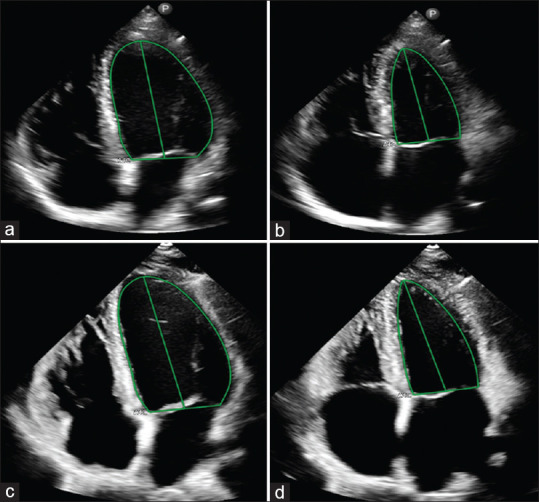

Methods: Twenty volunteers were scanned with HHE, standard echocardiography (SE), and CMR. LVEF and SV were measured with each modality, and their accuracy and precision were evaluated.

Abstract Image